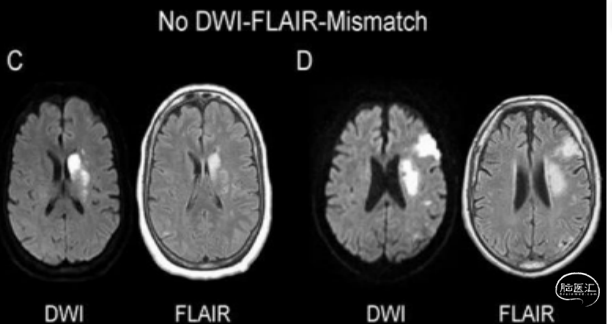

组织窗评估——DWI-FLAIR 错配:

存在 DWI-FLAIR 错配定义:DWI 显示高信号,FLAIR 信号改变不明显区域.

DWI-FLAIR 错配表明组织缺血时间在 4.5 小时内,可以作为静脉溶栓筛选指标,适用于醒后脑卒中患者进行溶栓决策。

不存在 DWI-FLAIR 错配:

DWI和FLAIR上相应区域均可见明显高信号 。适用于醒后或超时间窗脑卒中患者评估,不存在 DWI-FLAIR 错配说明不能进行静脉溶栓,溶栓获益较小而且出血风险增加。